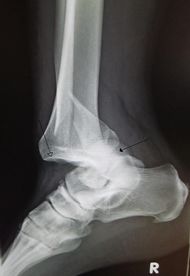

Ankledislocation.JPG

An traumatic dislocation of the tibiotalar joint of the ankle with distal fibular fracture. Open arrow marks the tibia and the closed arrow marks the talus.